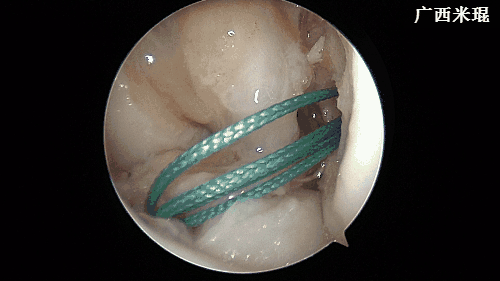

(十五)股骨端固定

关节镜确认后移植腱已经按照要求牵拉入隧道后,股骨端自横穿钉套管击入2枚横穿钉固定,拔除套管。此过程一般需要1~2分钟。